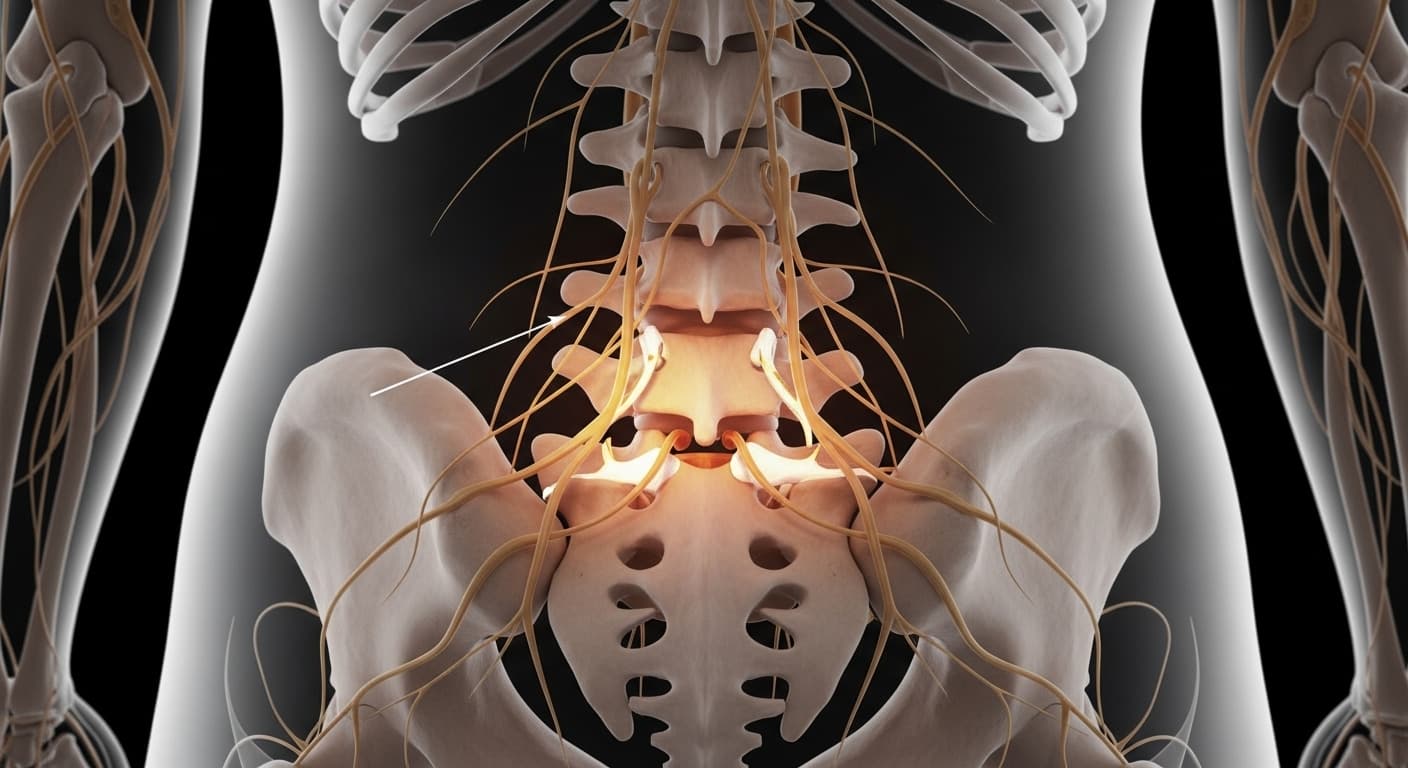

"평소 잘 걷던 길도 이제는 한 걸음 한 걸음이 두렵고, 다리가 저릿하고 힘이 풀려 주저앉을 뻔한 경험, 있으신가요? 허리 통증과 함께 다리까지 시큰거리거나 마비되는 듯한 느낌이 든다면, 혹시 척추관 협착증 때문은 아닌지 한번쯤 의심해볼 필요가 있어요."

현대 의학이 밝히는 척추관 협착증의 비밀